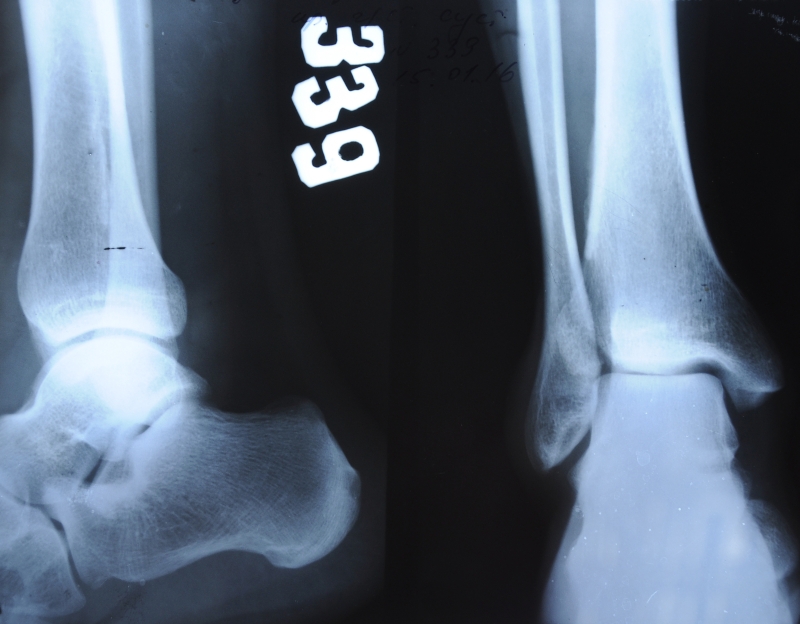

- Рентгенография помогает различить разрыв и растяжение связок.

Степень серьезности травмы определяется с помощью различных диагностических методов:

- Магнитно-резонансная томография и компьютерная томография позволяют оценить объем поврежденных тканей. На основе полученных данных устанавливаются характер и степень тяжести травмы.